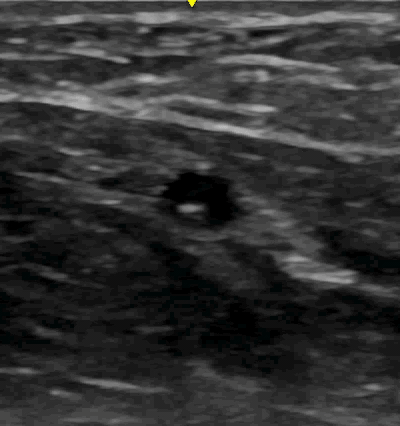

The major drawback of the transverse view is that the needle only appears as a dot on the screen no matter which part of the needle you are looking at (i.e. the needle tip appears the same as the middle of the shaft) as seen here.

Watch the needle tip enter the vein. Probably the hardest part of the procedure is making sure the little dot you see on the screen is the needle tip and not part of the shaft (while your needle tip is digging around somewhere deeper in the arm). I like to watch the wall of the vein compress as the needle hits it then pop back up once the needle enters. This will correspond to the flash of blood in the angiocath, but I have found this takes my eyes off the screen, I will probably lose that needle tip.